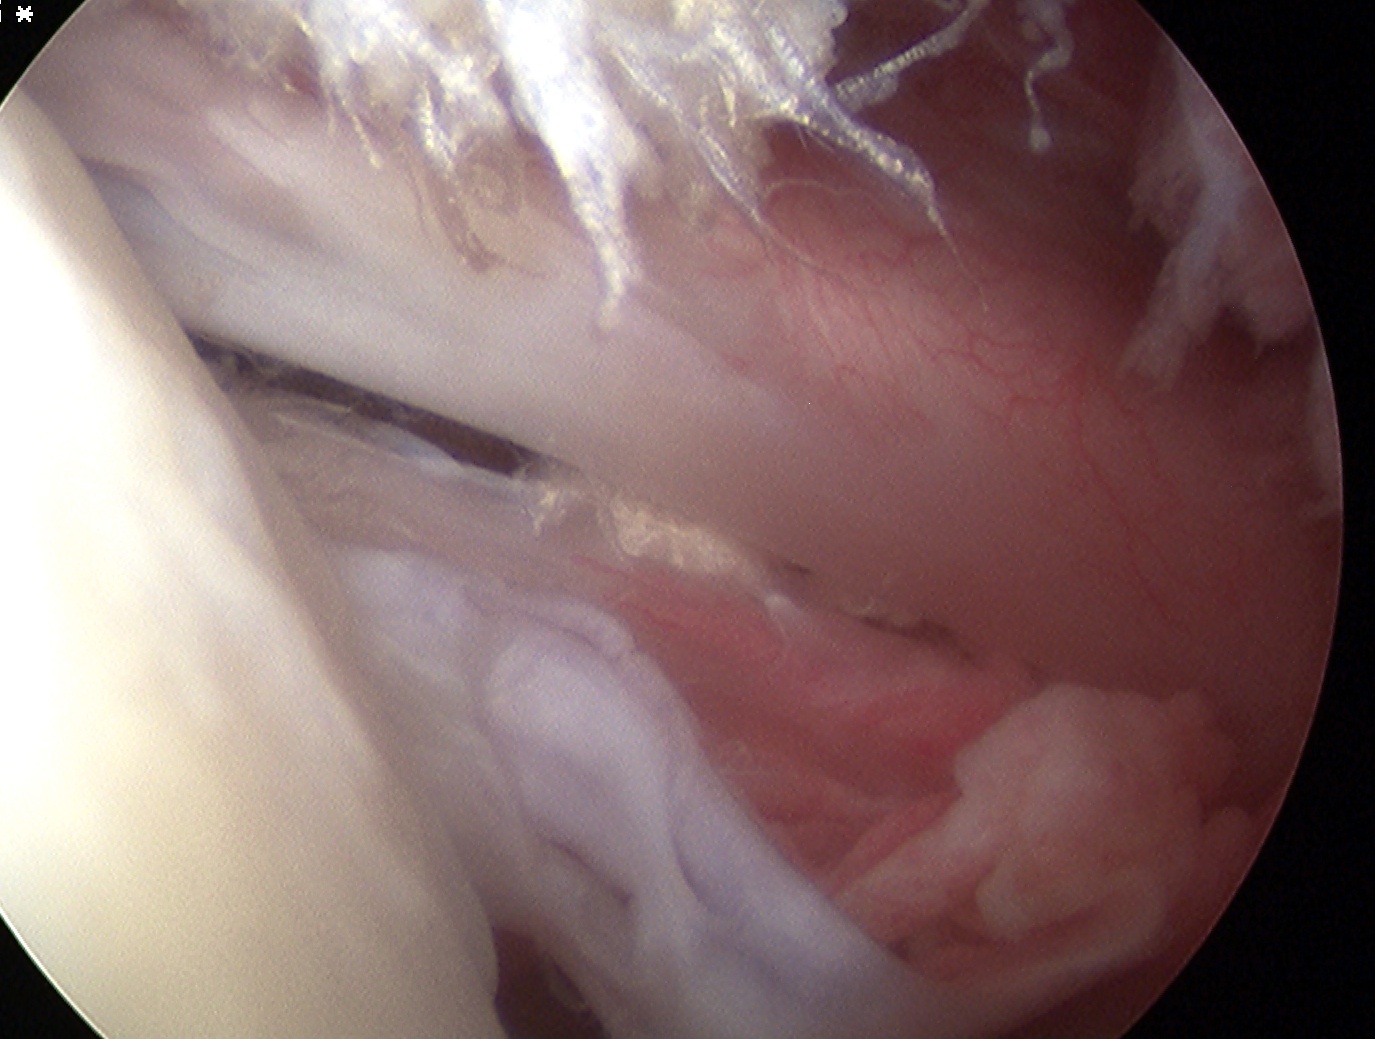

Comma sign

- medially retracted subscapularis tear

- exposes the superior insertion of superior glenohumeral ligament / coracohumeral ligament

Full thickness retracted subscapularis tear with comma sign